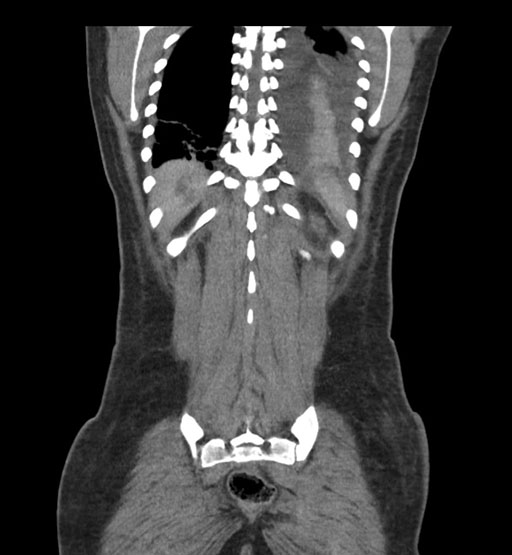

Coronal Arterial